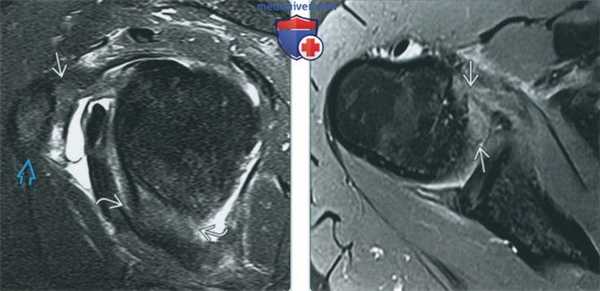

(Слева) МР-артрография в режиме PD FS, сагиттальный срез: визуализируются классические признаки адгезивного капсулита-заполнение пространства позади клювовидного отростка мягкими тканями и утолщение суставной капсулы в подмышечном завороте.

(Справа) МР-артрография в режиме PD FS, аксиальный срез: отмечается характерное утолщение суставной капсулы в подмышечном завороте.